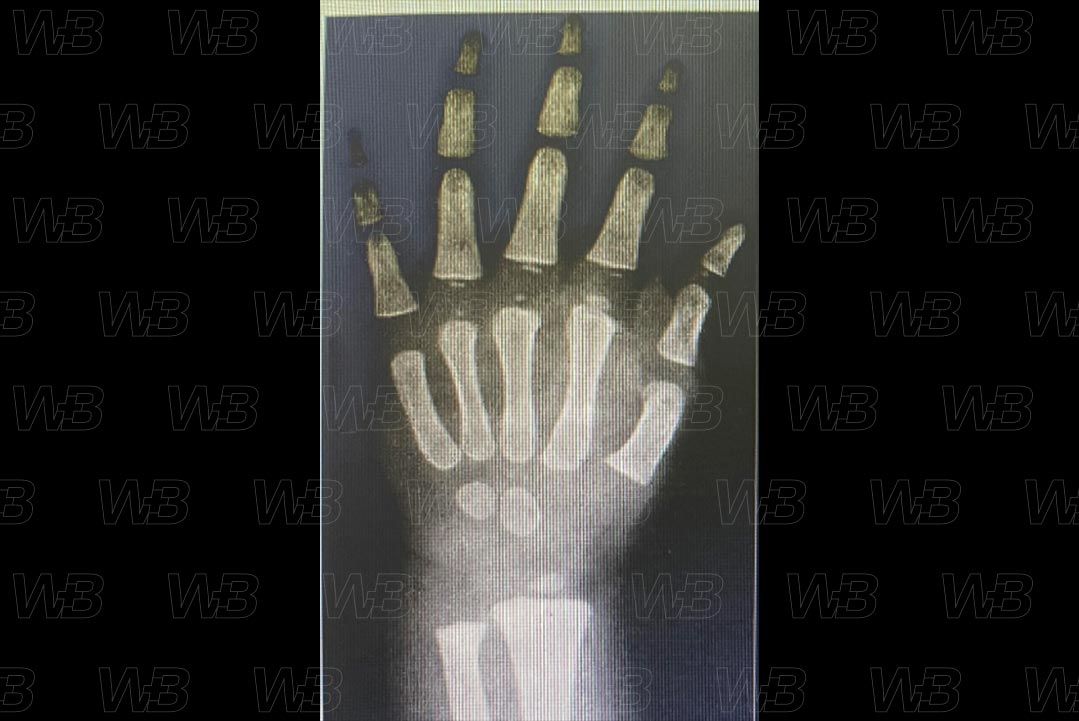

RADIOGRAFIA MÃOS E PUNHOS (IDADE ÓSSEA) [cms-watermark]

Feminino

1 ano e 6 meses:

• Epífise do quinto metacarpo e falanges proximal do quinto dedo, bem como falanges médias do segundo ao quinto dedos.